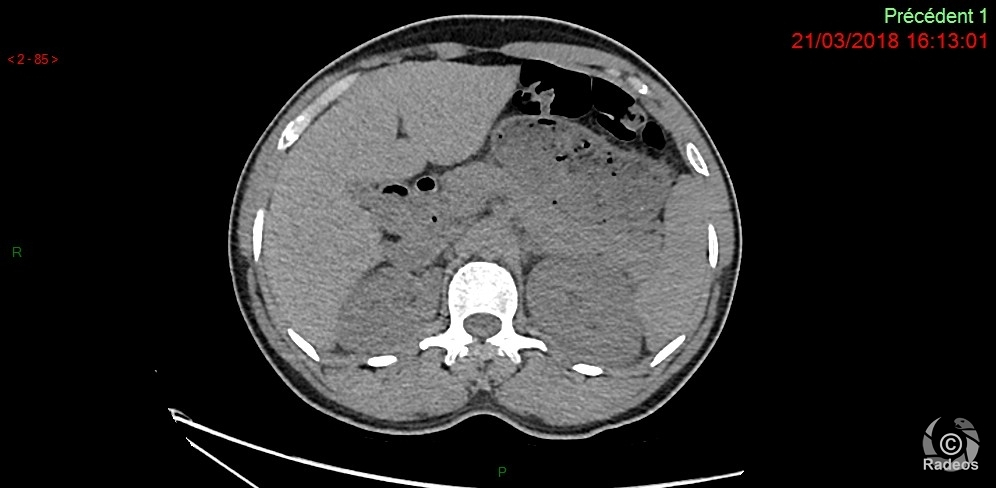

Aspect IRM d'une fibromatose profonde de la paroi abdominale. Découverte fortuite d'un angiome hépatique gauche.

Fibromatose profonde de type desmoïde